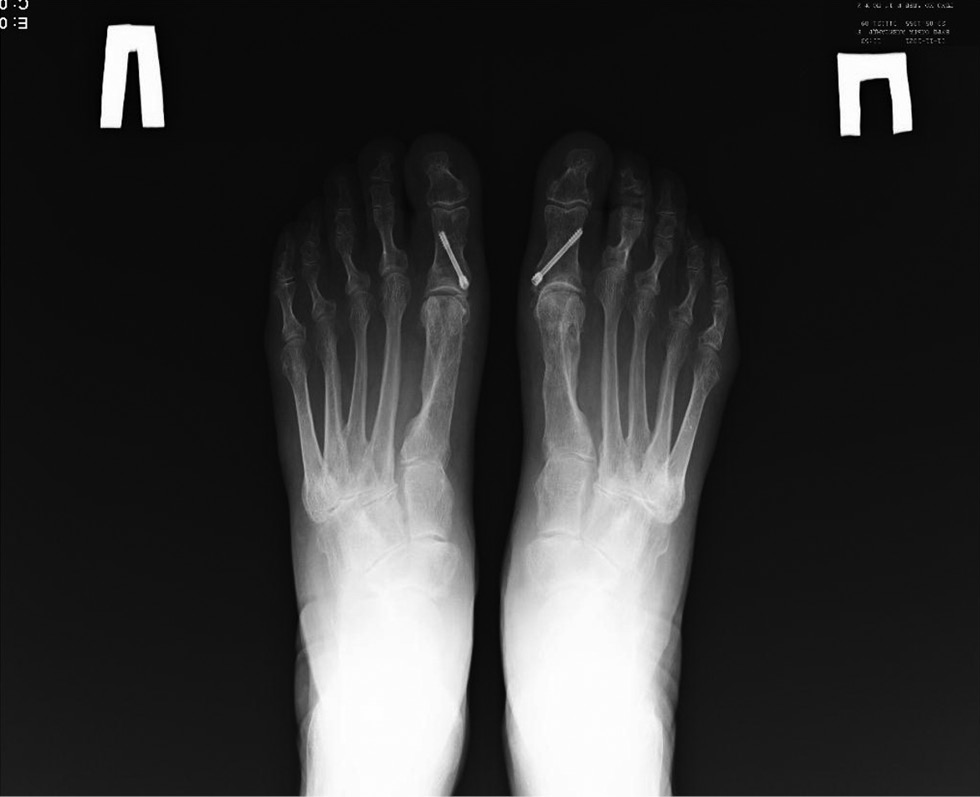

В 17 случаях (11,6%) в течение первого года потребовалось удаление винтов ввиду их миграции. На момент осмотра в 34 случаях (23,1%) было выполнено удаление металлофиксаторов. После проведённого контрольного осмотра 5 пациентам — 5 стоп (3,4%) — было запланировано хирургическое вмешательство для удаления металлофиксаторов (рис. 2).

Рис. 2. Рентгенограмма стоп через 5 лет после оперативного вмешательства. Удалённые металлофиксаторы первой плюсневой кости обеих стоп.

Fig. 2. Radiographs of feet 5 years after the surgical treatment. Screws removed from the 1st metatarsal bones of both feet.